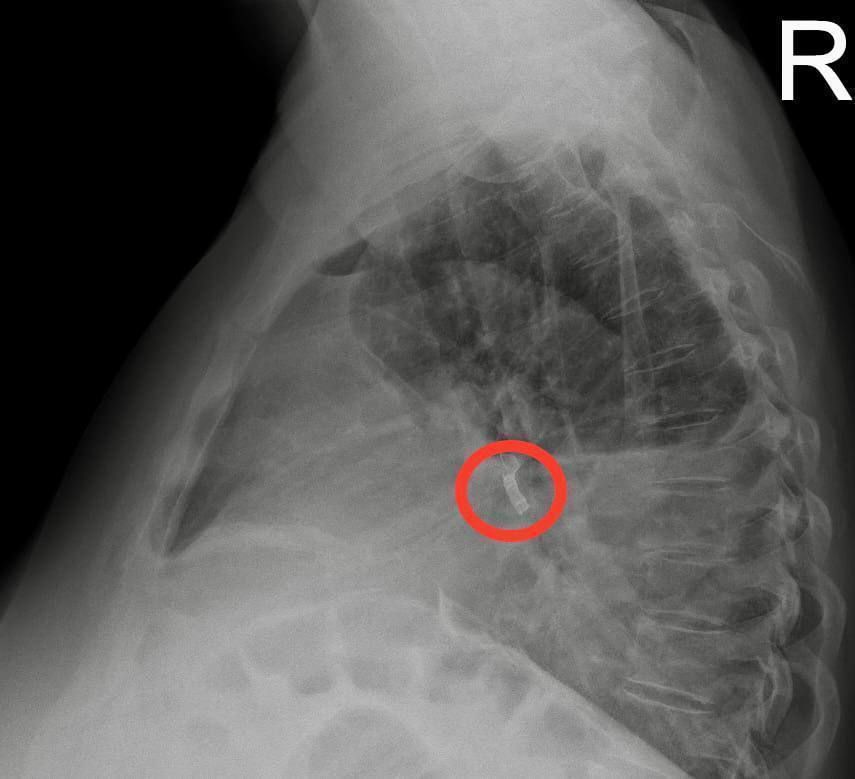

Врачи НИИ Джанелидзе сделали рентген, а затем и компьютерную томографию, которые показали, что в промежуточном бронхе справа находится инородное тело.

Как оказалось, около года назад женщина во сне вдохнула часть зубного протеза, не заметив этого, а впоследствии решила, что протез потеряла.

«За год нахождения в бронхе металлический предмет вызвал эмпиему плевры – гнойное воспаление плевральной полости, а также образование свища, через который началось распространение инфекции из легкого в плевральную полость», – рассказали в НИИ.

Дежурный хирург экстренно дренировал плевральную полость для оттока гноя, а затем заведующий эндоскопическим отделением отдела неотложной хирургии НИИ Муса Сафоев провел операцию по удалению зубного протеза длиной около 1,5 сантиметра.